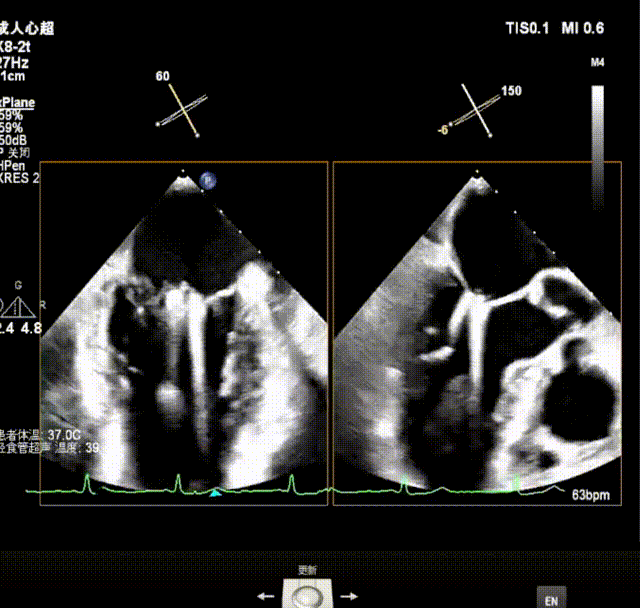

X-plane视窗可见二尖瓣瓣叶“连枷样”运动;

3D enface view示二尖瓣内后叶2偏1区瓣尖可见断裂的腱索呈“连枷样”运动,偏心性返流

3D模式测量二尖瓣瓣口面积5.62cm²术前TEE房间隔高度约4.72cm

瓣上M/L和A/P调整瓣膜夹,在X-plane进行超声确认(视频),进行弹道路径检查;

3D指示下调整瓣膜夹朝向病变区域